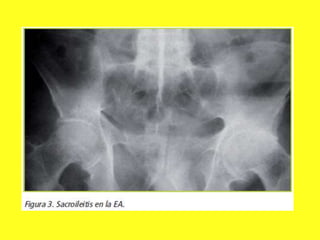

• 43. Cuales son los hallazgos más comunes en imagen obtenidas en la espondilitis anquilosante?

 R = Erosiones y esclerosis sacroiliacas, IMAGEN EN COLUMNA DE BAMBU